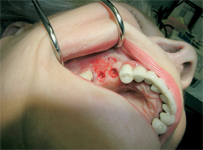

Velmi často je pro zavedení implantátu vzhledem k nedostatku kosti provést její doplnění tzv. augmentaci. Naše zařízení je zaměřené na doplnění nedostatečného množství kosti a používá celou řadu moderních postupů metod a matriálů. Velký význam pro úspěšné doplnění kosti hraje i dostatečné množství měkkých tkání – sliznice, která musí dodané množství kosti dokonale překrýt a nesmí ani tlakem způsobit jeho resorpci. Jednou z nejmodernějších a velice šetrnou metodou pro získání dostatečného množství měkkých tkání je použití osmotického hydrogelového expanderu.